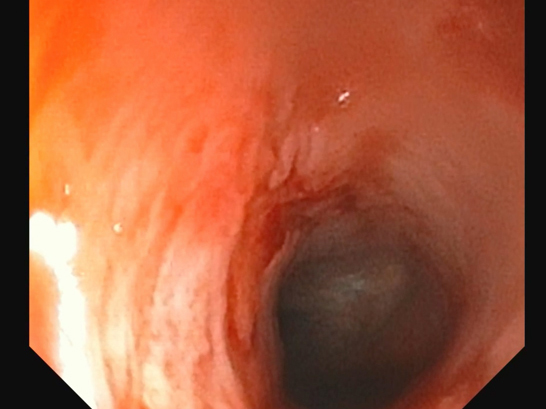

約3ヶ月前より鼻炎症状を主訴に他院を受診し、鼻炎としての治療が行われたものの、十分な改善が見られなかったため、精査を目的として当院を受診されました。 当院にてCT検査を実施したところ、鼻咽頭部に顕著な狭窄を認めたことから、呼吸器症状の改善を目的に、鼻咽頭狭窄に対するバルーン拡張術を実施しました。 処置後の経過は良好で、全身状態も安定していたため当日退院としました。 その後も経過観察を継続しており、現在までに7ヶ月が経過しましたが、再発は認められていません。

拡張後の鼻咽頭部